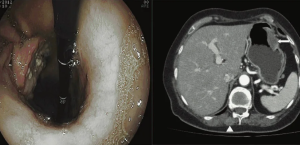

Наряду с уже распространенными методами медицинской визуализации, такими как рентгеноскопия, ФГДС, УЗИ и КТ, при заболеваниях желудка в последнее время все чаще используется МРТ (пока на втором этапе диагностического алгоритма). Основной задачей МРТ является, прежде всего, оценка степени изменения стенки желудка, стадирование патологического процесса с обнаружением как местных, так и отдаленных метастазов.

Методика исследования желудка включает в себя два этапа с предварительной подготовкой. Подготовка пациента к исследованию: за день до исследования исключить пищу богатую клетчаткой, принять «Фортранс», вечером выпить две таблетки «Но-шпы», очистительная клизма. Утром исследование проводится натощак с приемом двух таблеток «Но-шпы» за 20 минут до процедуры. Первый этап проводится на пустой желудок с использованием стандартных программ в коро- нальной, аксиальной и сагиттальной плоскостях взвешенных по Т2, Т1 с жироподавлением. На данном этапе оценивается состояние органов брюшной полости и забрюшинного пространства, диафрагмы, регионарных лимфоузлов, форма и расположение желудка, перигастральная клетчатка и абдоминальный отдел пищевода. Второй этап проводится при наполненном желудке. В качестве наполнителя используется обычная вода температуры 3б-37оС в количестве 3-4 стакана по 150 ml (450-600 ml).

Снова оценивается положение осей желудка, и срезы выставляются строго по осям, используя Т2ВИ. При нахождении подозрительного участка стенки желудка устанавливаются срезы толщиной до 3 мм параллельно и перпендикулярно патологической зоне, что позволяет определить протяженность поражения стенки, ее толщину, глубину поражения, наличие изъязвлений и нарушение целостности серозного слоя. В дополнение к Т2ВИ используются программы Т1 TRUFI и DWI.